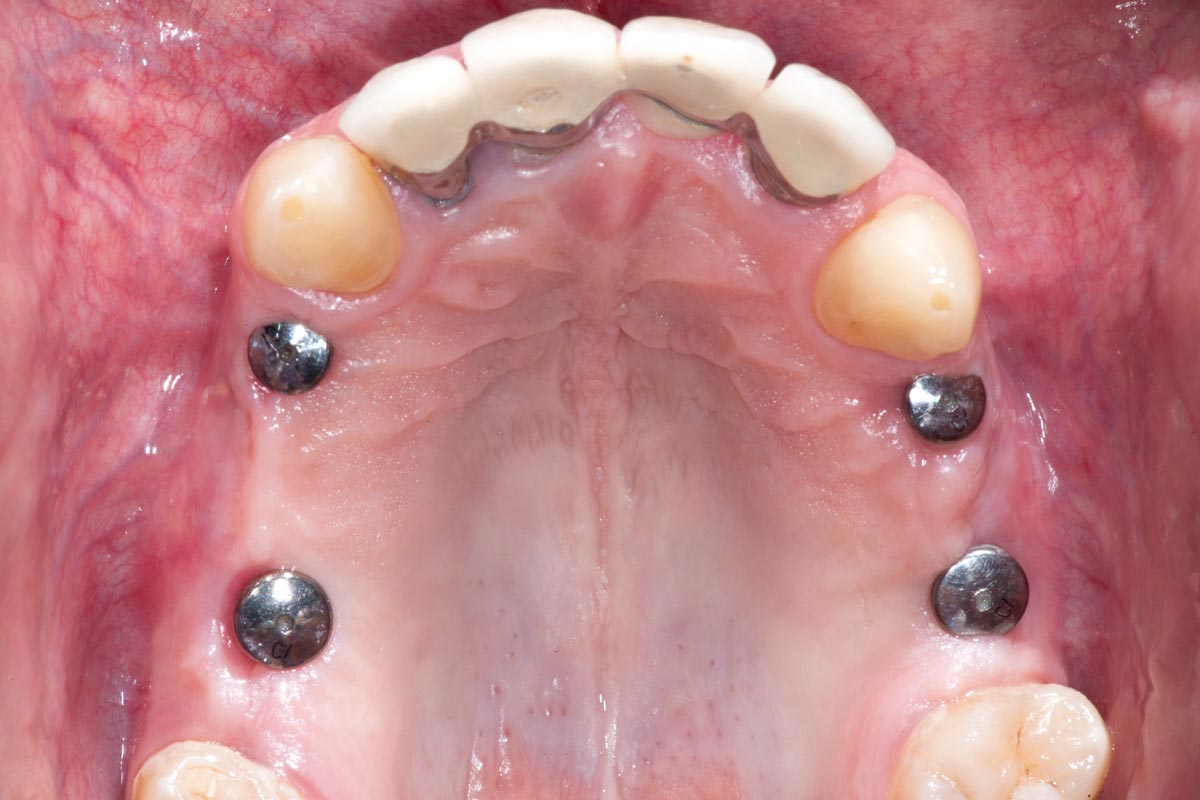

Augmentation of buccal and lingual bone lamella with maxgraft® bonering - Dr. B. Giesenhagen

X-ray scan: initial situation loss of two wall bony defect with loss of buccal and lingual lamella